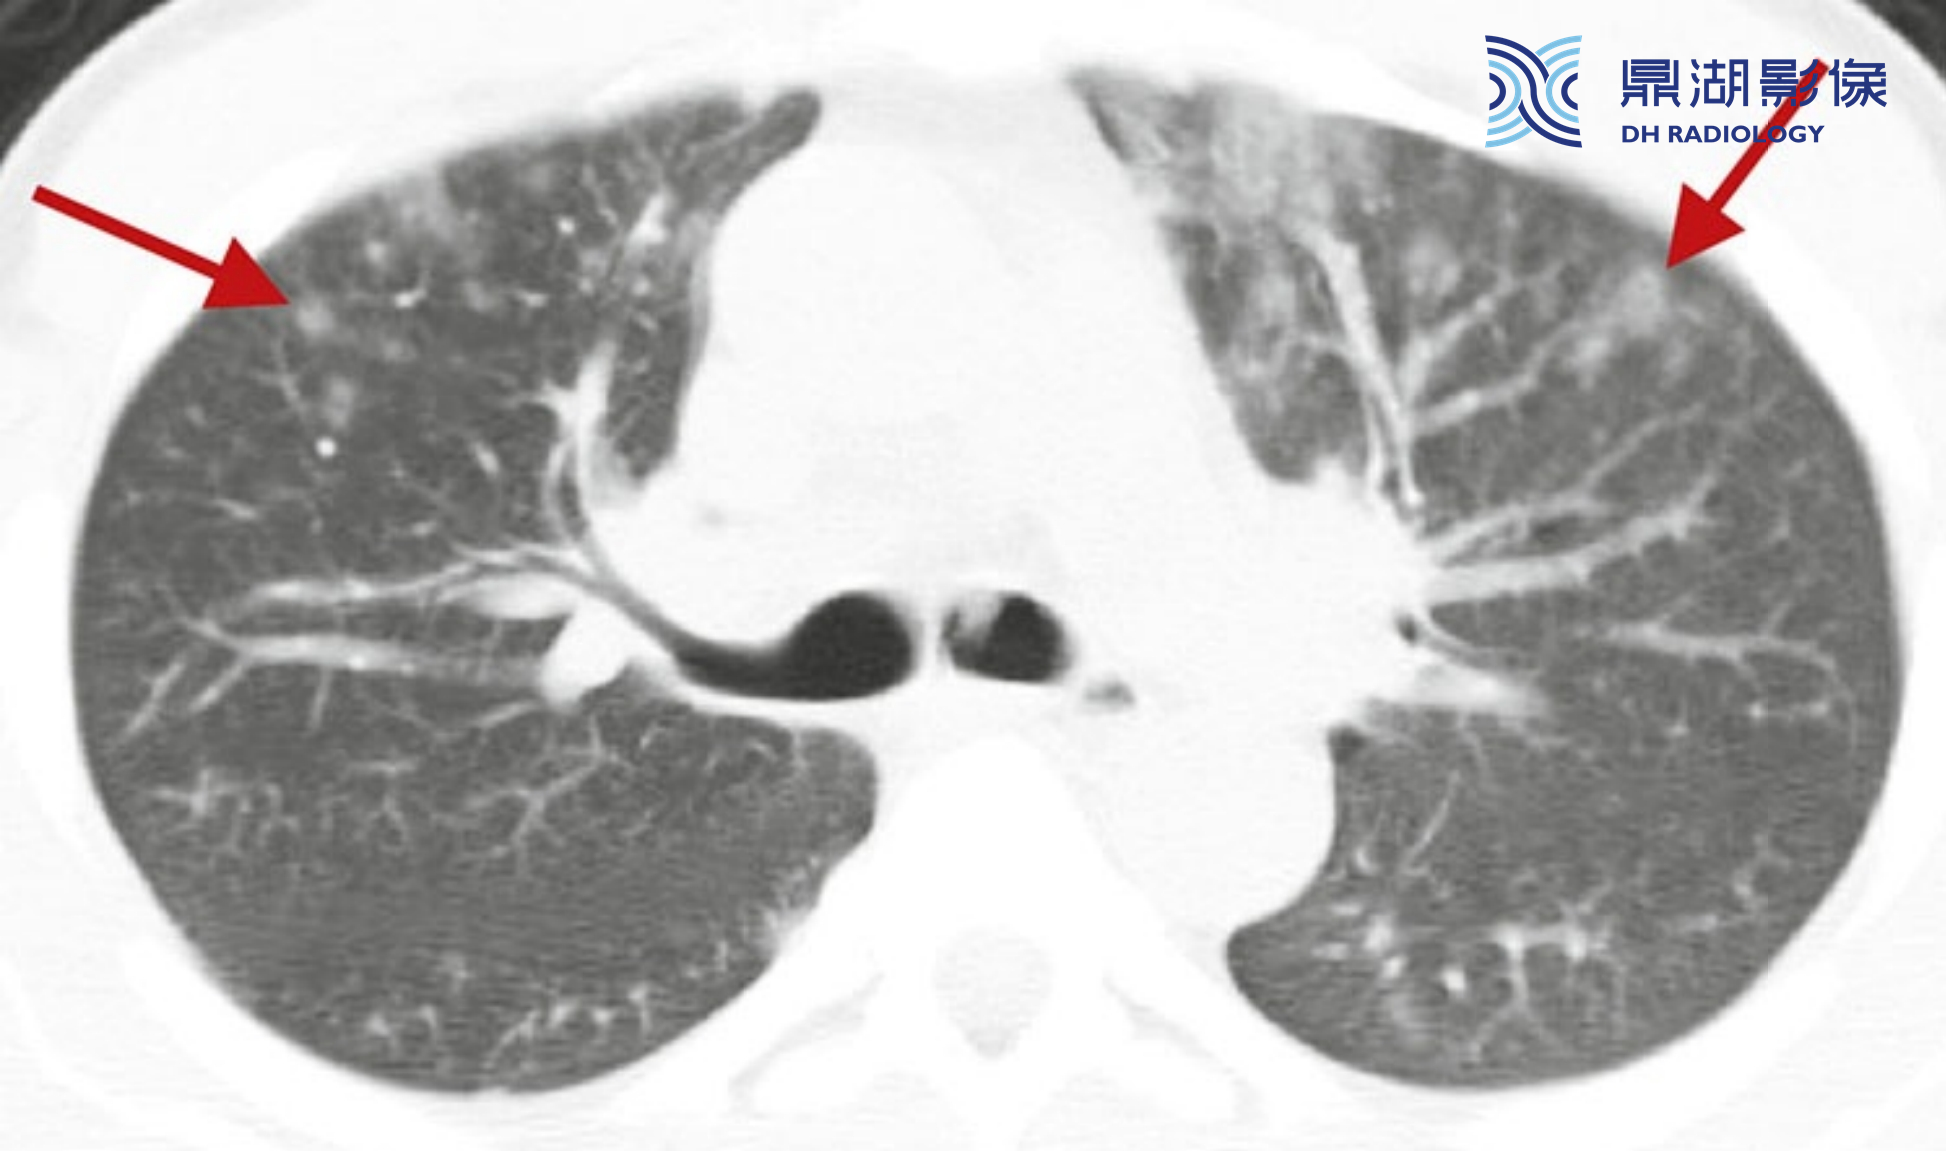

23225ead85139f36e42e56c35b142f24.png

表现为小叶中心性结节的肺水肿。双侧肺前部可见边界不清的小叶中心性GGO结节(箭),这并不是肺水肿的少见表现,且常伴有肺泡性肺水肿的其他表现。